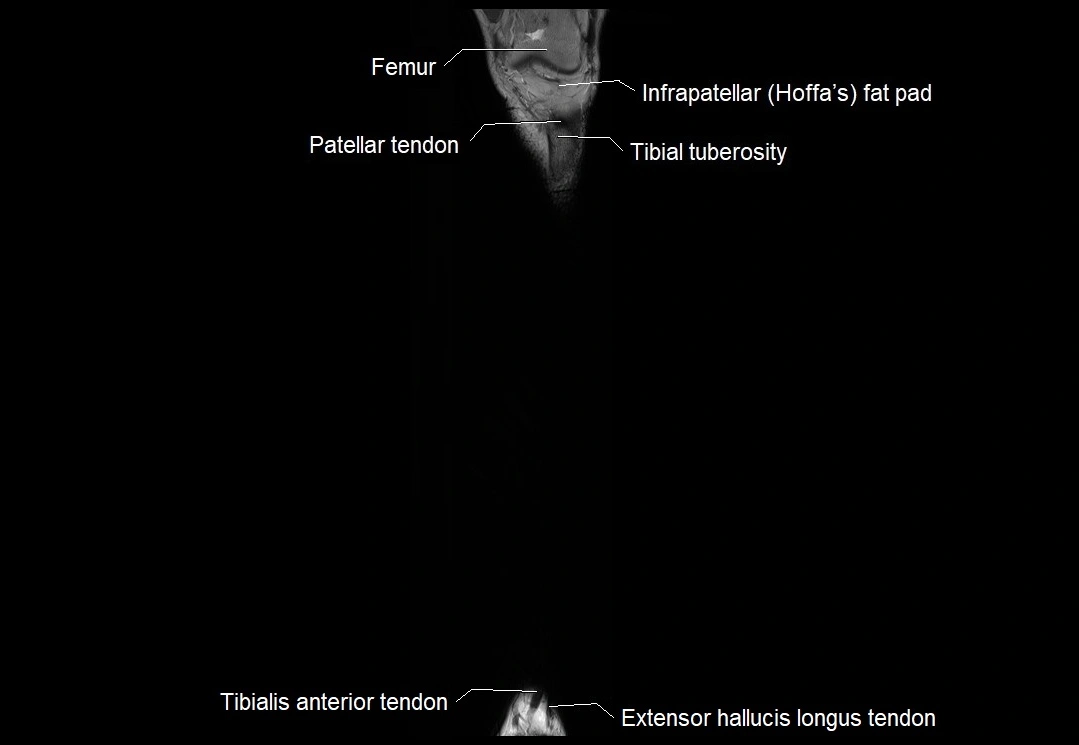

MRI image